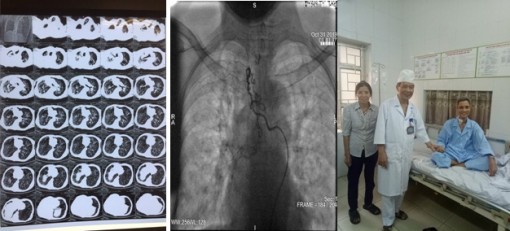

Cứu sống bệnh nhân "ho ra máu sét đánh"

Đây là kỳ tích trong thực hành lâm sàng, vì bệnh nhân ho ra máu rất nặng, tỷ lệ tử vong gần như 100% do tình trạng tắc nghẽn đường thở cấp tính dù được cấp cứu kịp thời, nên được y văn gọi là ho ra máu sét đánh.